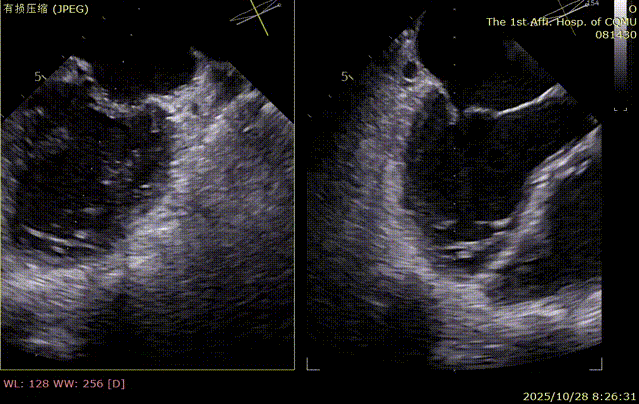

入院后超声诊断:二尖瓣重度反流(4+);三尖瓣重度反流;心力衰竭;左房、右心增大。

术前食道超声评估:三尖瓣重度反流,FTR6+,反流位于前隔、中央,后隔。瓣叶粘液样变性,后隔可见4.6mm gap。

二尖瓣术前评估

复查TTE及TEE检查进一步评估二尖瓣情况。明确为FMR( Carpentier Ⅲb型),二尖瓣后叶栓系,2区瓣叶运动(视频2),重度FMR(4+), 肺静脉逆向血流;2区后叶长度1.15cm,2区前叶长度2.46cm,AP径3.2cm,瓣口面积5.1cm²,房间隔高度3.95cm,瓣叶无钙化,二尖瓣瓣膜条件适合行TEER手术。

图1、图2:2区瓣叶长度(前叶长度2.46cm,后叶长度1.15cm)及彩色血流